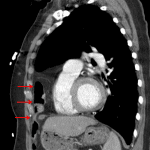

- Large Morgagni hernia containing bowel

- Platelike compressive atelectasis in the right lung base

- No pleural effusion or pneumothorax

- Mild enlargement of the cardiopericardial silhouette

- Morgagni hernia

Large Morgagni hernia containing bowel. CT could provide further characterization, particularly if there is clinical concern for bowel ischemia or obstruction.

Compressive atelectasis in the right lung base without additional evidence of acute cardiopulmonary disease.